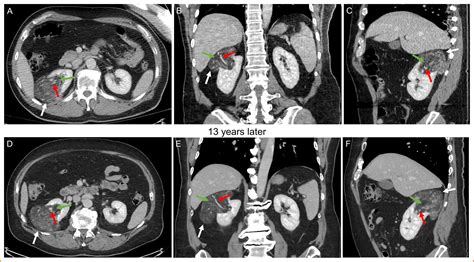

A Kidney AML tumor is a type of mesenchymal tumor, which means it arises from the soft tissues of the kidney rather than the filtering units themselves. Because these tumors contain fat, they have a unique appearance on medical imaging tests like CT scans or MRIs, which helps radiologists distinguish them from potentially cancerous kidney tumors. Most angiomyolipomas occur sporadically, meaning they appear spontaneously without a clear hereditary link. However, a significant subset of patients develops these tumors in association with a genetic disorder known as Tuberous Sclerosis Complex (TSC). In patients with TSC, these tumors are often more numerous, larger, and more likely to affect both kidneys.

While benign, the "behavior" of a Kidney AML tumor depends largely on its size and composition. Smaller tumors often cause no symptoms and may remain stable for many years. However, larger tumors—specifically those measuring over 4 centimeters—pose a higher risk of complications, such as spontaneous bleeding, due to the abnormal, fragile blood vessels they contain. For this reason, clinical management focuses on active surveillance to ensure the tumor does not reach a size where it becomes dangerous.

Diagnosing a Kidney AML tumor involves various imaging modalities to assess the size and character of the lesion. A CT scan with contrast or an MRI is typically the gold standard because these scans can identify the presence of fat within the tumor—a hallmark characteristic of an angiomyolipoma.

For small, asymptomatic tumors, the standard approach is “watchful waiting.” This involves regular imaging—typically an annual or biannual ultrasound or CT scan—to monitor the growth rate. If the tumor remains stable, no invasive intervention is necessary. This approach minimizes risks associated with surgery or medical procedures.